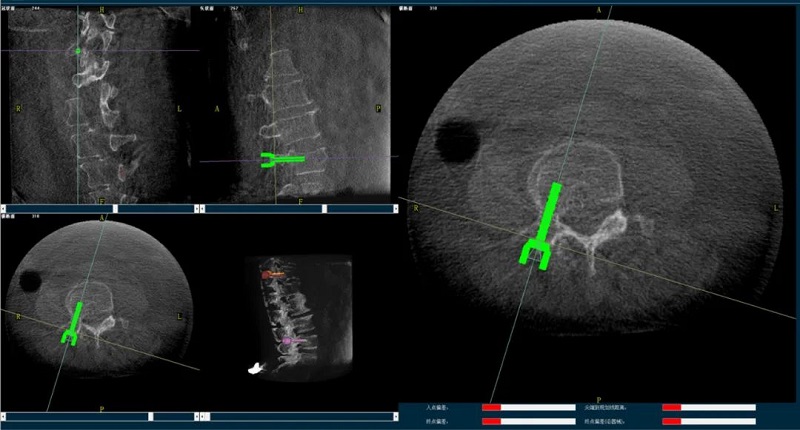

一旦圖像配準完成,手術導航系統會將手術器械的虛擬圖像與術中獲取的三維影像進行重疊顯示。隨著醫生移動真實的手術器械,其對應的虛擬圖像也能在三維CT影像上實現實時同步移動。

通過觀察手術導航系統的屏幕,醫生能夠實時地掌握器械與患者手術部位的解剖結構的相對位置關系。這一信息至關重要,它幫助醫生精確評估手術器械與目標手術點的距離,從而沿著預先規劃的手術路徑,精準地進行手術操作。